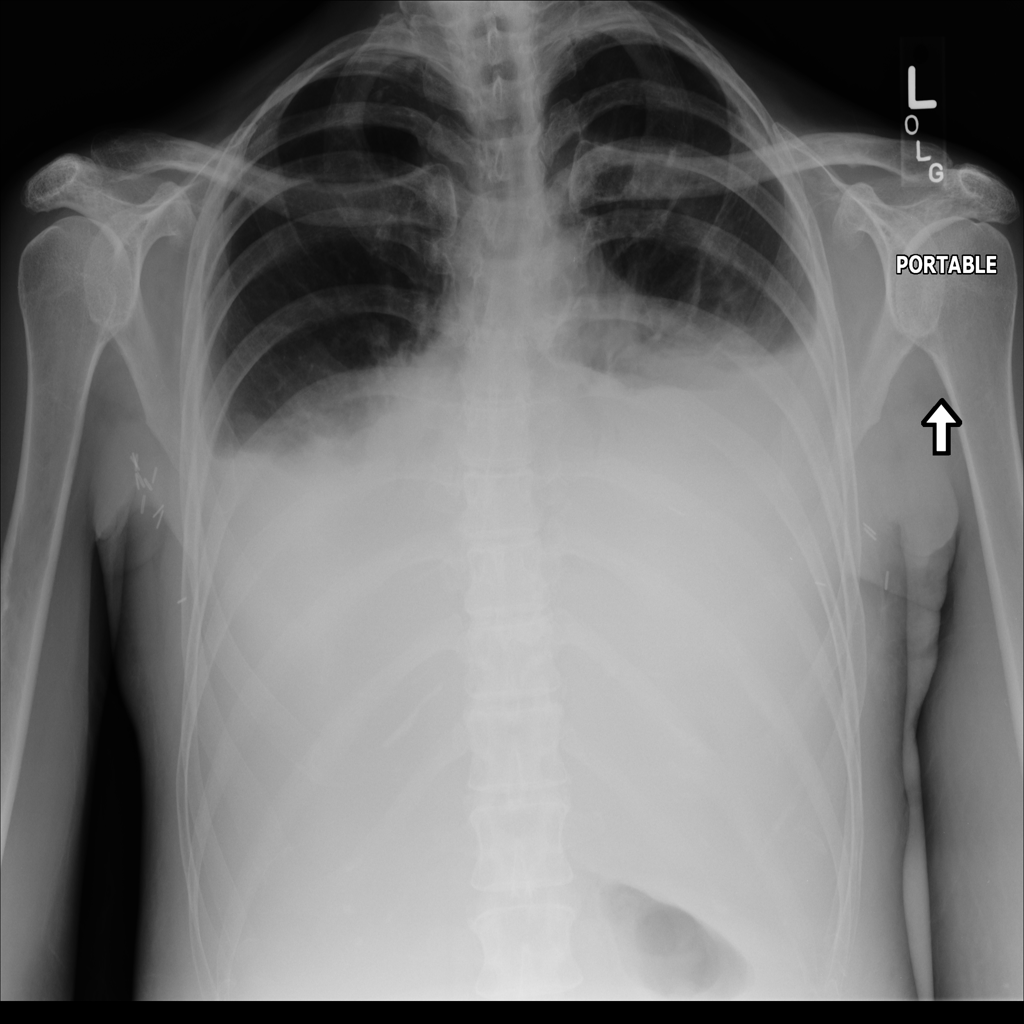

PAT-3795 · IMG-003Effusion

PAT-3795 · IMG-003

AP